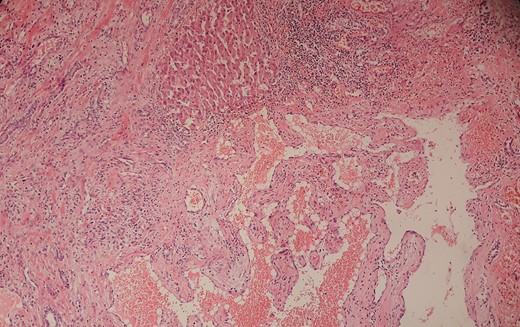

A 49-year-old female, with no co-morbid illness, presented with 3 months history of fever. The fever was intermittent, low grade (maximum temperature recorded 101 degree Fahrenheit) with an evening rise and not associated with chills and rigor. She denied any history of pain abdomen, cough, dysuria, joint pain, weight loss or loss of appetite. General physical examination including chest did not reveal any significant findings. On palpation of abdomen, there was a vague, non-tender, ill-defined lump in the epigastric region. Laboratory investigation including hemoglobin (12.6 gm/dl), total leukocytes counts (9200 cells/mm3), renal and liver function tests were within normal range. Blood cultures, sputum and urine culture were sterile. Moreover, the extensive infectious and immunological workup including tuberculosis, malaria, kala-azar and HIV were negative. Chest X-ray was also normal. The contrast enhanced computed tomography of abdomen revealed a peripheral nodular enhancing lesion measuring 15 cm × 11 cm, with central hypodense areas in left lateral segment of the liver suggesting giant hemangioma (Fig. 1). Liver hemangioma as a cause for fever of unknown origin was assumed (after excluding all other causes) and underwent laparoscopic assisted left lateral segmentectomy (Fig. 2). Histopathological report confirmed cavernous hemangioma of liver (Fig. 3). Patient did well and was discharged on postoperative Day 5. At 3 months of follow-up, patient was afebrile.

(H&E, ×100) Pathological examination confirmed the diagnosis of cavernous hemangioma.